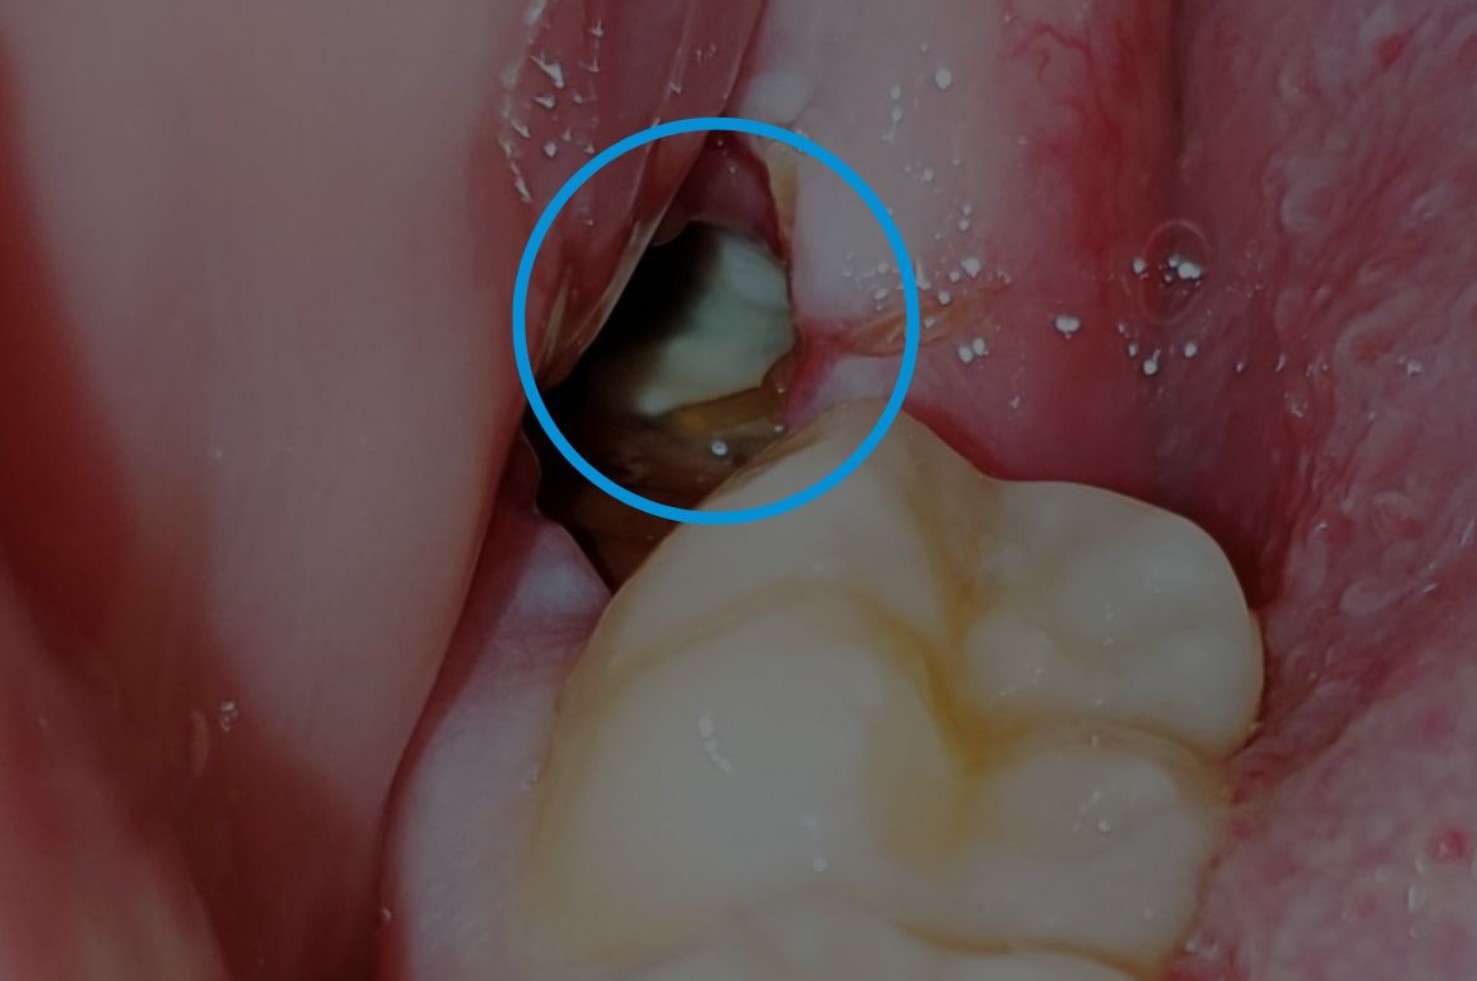

Lợi trùm là tình trạng mô nướu (lợi) ở phía trong cùng của hàm phủ lên một phần hoặc toàn bộ mặt răng khôn khi chiếc răng này đang trong quá trình mọc. Phần lợi này tạo thành một “nắp che” khiến thức ăn, vi khuẩn và mảnh vụn dễ bị kẹt lại bên dưới, từ đó gây viêm, sưng, đau hoặc thậm chí mưng mủ.

Hiện tượng này thường xảy ra ở răng khôn hàm dưới, do vị trí mọc bị giới hạn và góc nghiêng của răng phức tạp hơn so với các răng khác.

- Lợi trùm bán phần: phần nướu chỉ che phủ một phần mặt răng, răng vẫn có thể trồi lên được nhưng dễ tích tụ vi khuẩn gây viêm.

- Lợi trùm toàn phần: phần nướu che phủ hoàn toàn mặt răng khôn, khiến răng không thể mọc lên và dễ dẫn đến viêm nặng.

- Phần lợi phía sau có thể nhìn thấy lớp màng mỏng che phủ răng, gọi là “mũ lợi”.